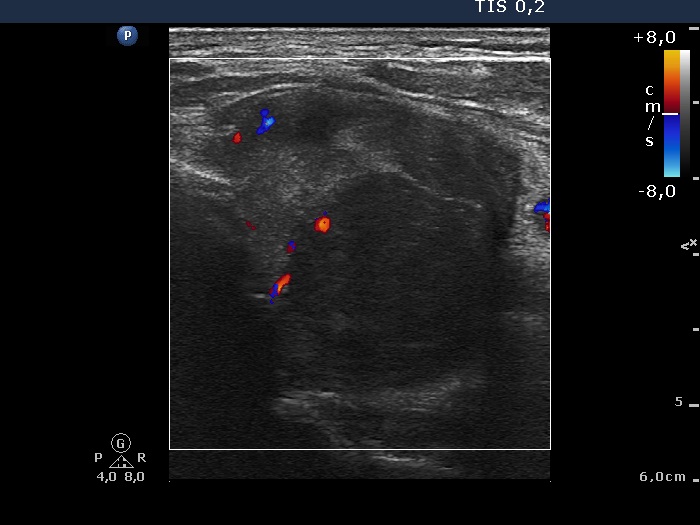

Ultrasonography revealed that the palpable mass contained the enlarged left thyroid composed of a large hypoechogenic nodule with irregular borders and multiple irregular lymph nodes in the left side of the neck.